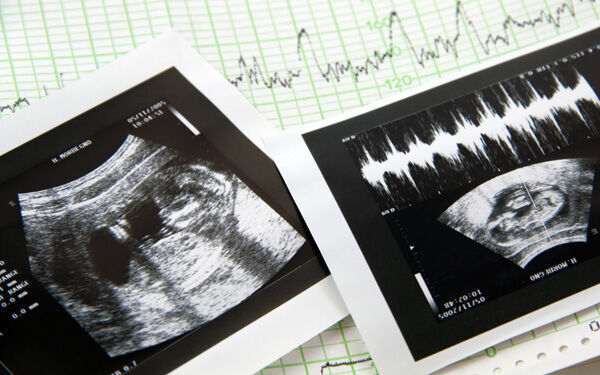

· 妊娠5週目~妊娠15週目 (妊娠初期)のエコー写真 妊娠初期 (5週目~15週目)の超音波エコー写真を紹介します。 井上裕子先生 プロフィール 東京都立川市 井上レディスクリニック院長。 産婦人科専門医、日本乳癌学会認定医、認定健康スポーツ医 · 妊娠4ヶ月(12週~15週目)のお腹の大きさ&体重&エコー写真 今日で妊娠15週6日目、明日からは安定期と呼ばれる妊娠5ヶ月目に突入です。 もうね、最近本当にぐーたらした生活を送っておりまして(´ω`。 · 妊娠5ヶ月、もうすぐお別れすることになりました。 テーマ: 第二子妊娠記録無頭蓋症 前回の記事で妊娠をお伝えしました。 現在私は、妊娠4ヶ月の末、 あと数日で安定期というところです。 胎児ネームは「セカンドたまちゃん」 第一子の時、私

1404 · 妊娠初期のエコー検査で見られるダウン症の特徴の1つに、赤ちゃんの頸部(首)のうしろにある皮下組織に観察されるむくみ(浮腫)が挙げられ、むくみの部分の画像は黒く抜けて観察されます。 むくみは英語のNuchal Translucencyの略語として「NT」や正式 · 4dエコーの料金の相場は5,000〜,000円です。 3d写真とのセット料金もあるので、病院に問い合わせるのが一番いいですね。 赤ちゃん4dエコーはいつからいつまで? 4dエコーに適した時期は、 早くても妊娠14週から、遅くても32週ごろ までです。 · 1505 「首の後ろに空間が」 妊娠4ヶ月で先天性異常の可能性を指摘され、夫婦で出した結論 妊娠・出産 不安やリスク その他不安やリスク 妊娠初期 妊娠4ヶ月 25歳~29歳 編集部 長女を妊娠したときはフルタイムの正社員として勤務していたため

1401 · 妊娠4ヶ月(妊娠12週、13週、14週、15週)の胎児と母体の状態 妊娠4ヶ月になると、いよいよ「胎盤」が完成! 胎児の発達は加速します。胎盤の役割とは? 赤ちゃんの性別はいつわかるの? ママはつわりがおさまってきて食欲増進。3006 · エコーでわかる? 時期は? 気になる先輩ママの実話 安定期に入ると、気になってくるのが赤ちゃんの性別ですよね。 男の子、女の子、どちらの性別なのか、ママやパパはワクワクドキドキしていることでしょう。 一般的に、赤ちゃんの性別はいつごろ判明するのでしょうか。 エコー(超音波)検査で確実にわかるものなのでしょうか。 ここでは、赤ちゃんの妊娠4ヶ月(妊娠12週、13週、14週、15週)の胎児と母体の状態 妊娠4ヶ月、赤ちゃんの命綱である「胎盤」がついに完成! 胎児の発達は加速します。 ミラクルな胎盤の役割とは? 赤ちゃんの性別は? 一方、ママはつわりもそろそろおさまって、食欲が湧いてくるころ。 食生活を見直して、体重管理を! 母親学級に参加したり、マタニティライフも楽しんだり